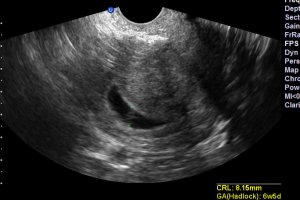

February to March 2016: Frozen embryo transfer cycle (2 embryos) with acupuncture, results in twin pregnancy. (Embryo transfer #9)

April 2016: Baby A heartbeat stops close to 8 weeks. Baby B heartbeat stops unexpectedly right before 10 weeks. Followed by D&C procedure.